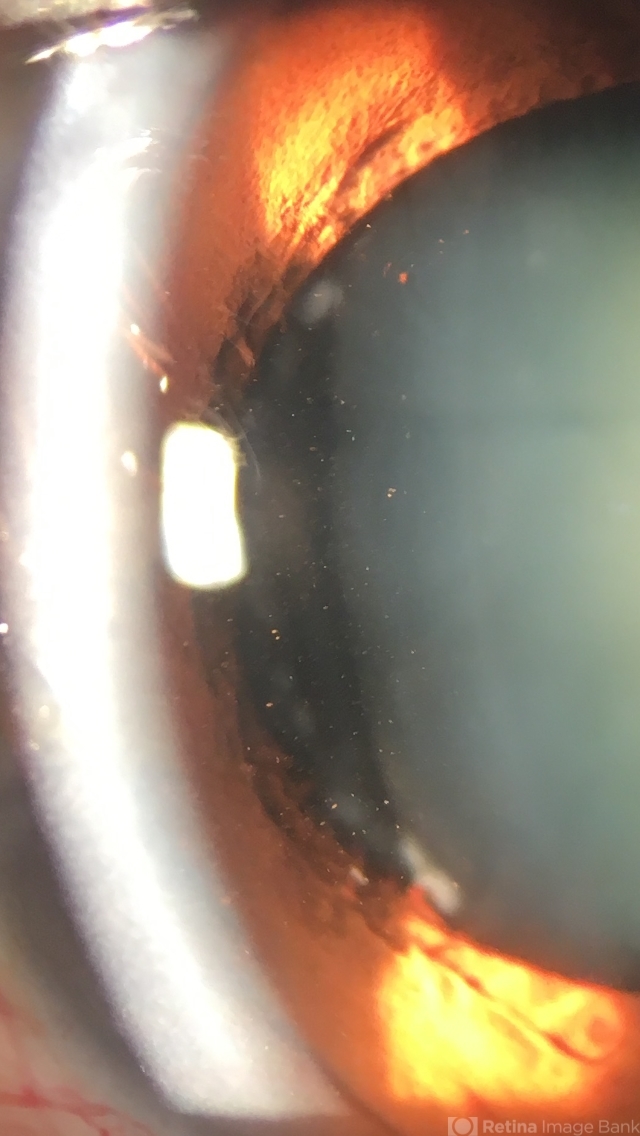

- laser, crystalline lens

- Spot opacities probably produced by laser application